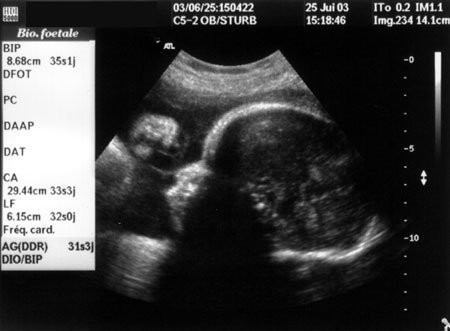

Le 25 juin 2003, à 31 semaines et trois jours de grossesse, le bébé fait environ 2,200 kg.

(Florent à peu près au même stade)